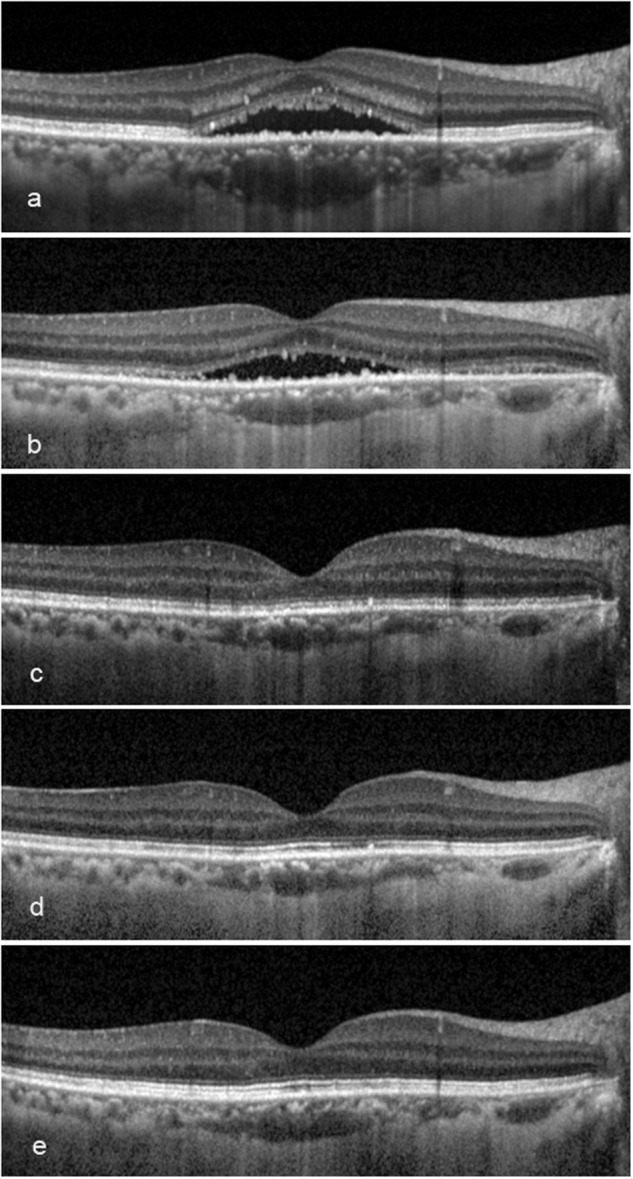

Fig. 5.

The outer retinal microstructure recovery post treatment of a 43-year-old female with symptom duration for 6 months. a At baseline, ellipsoid zone (EZ): absent, interdigitation zone (IZ): absent; b, c at 3 and 6 months, EZ: fragmented, IZ: absent; d at 12 months, EZ: continuous, IZ: absent; e at 24 months, EZ: continuous, IZ: fragmented. The subretinal fluid at baseline had been partly absorbed at 3 months, and completely absorbed at 6 months. The external limiting membrane presented continuous along the whole follow-up. The best-corrected visual acuity (logarithms of the minimum angle of resolution) was 0.22, 0.10, 0.00, −0.10 and −0.30 at each visit